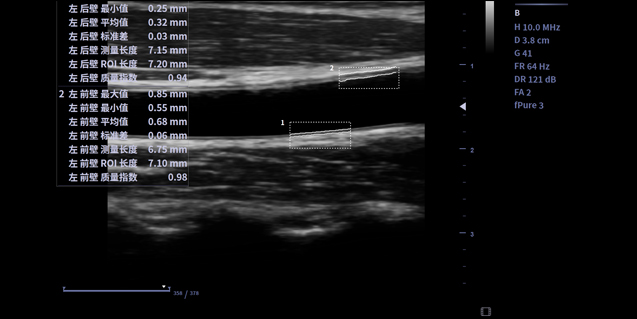

适用于浅表组织、小器官,神经,血管等

256阵元数,61.5*23.4成像范围,更适用于乳腺扫查。

IBS技术使得探头灵敏度和带宽均提高40%,一致性提升37%,长期稳定性提升42%